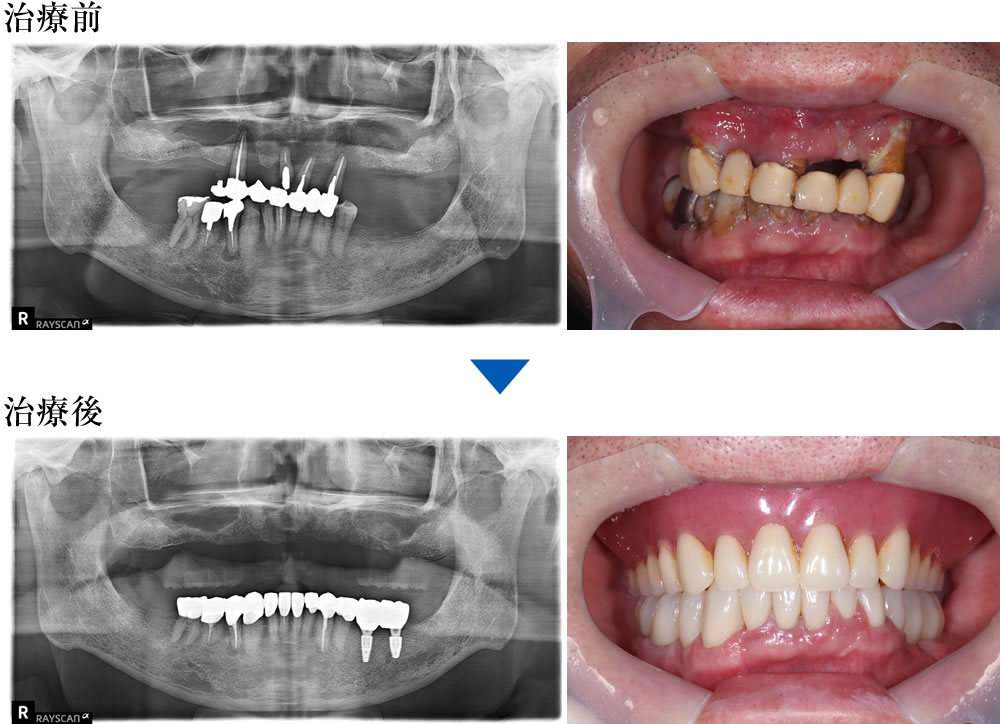

重度歯周炎の患者に対して実施した咬合再構成の症例

こちらの患者さまは、上の歯が抜けそうとの主訴で来院されました。上顎ブリッジが大きく動揺している状態、下の歯は動揺はありませんでしたが、全体的に虫歯や歯石の沈着が確認できました。

レントゲン精査を実施。上顎残存歯は歯を支える骨がほとんどなくなっており、保存するのは不可能な状態(重度歯周炎)と診断しました。

治療前後の比較

術前と比較して咬み合わせが安定しました。歯の傾斜も改善され、審美的にも患者さまにご満足いただけました。下顎は補綴前に必要部位の根管治療を行っています。X線写真上、下顎右4番の根尖病変は縮小傾向を示しています。

| 年齢・性別 | 60代 男性 |

|---|---|

| 治療期間 | 8ヵ月 |

| 治療回数 | 25回 |

| 治療費(税込) | 2,420,000円(別途上顎は保険の義歯の費用) |

| リスク・注意点 | ・外科処置には術後麻痺等のリスクがあります。 ・骨の状態によっては治療期間が長くなる場合があります。 |